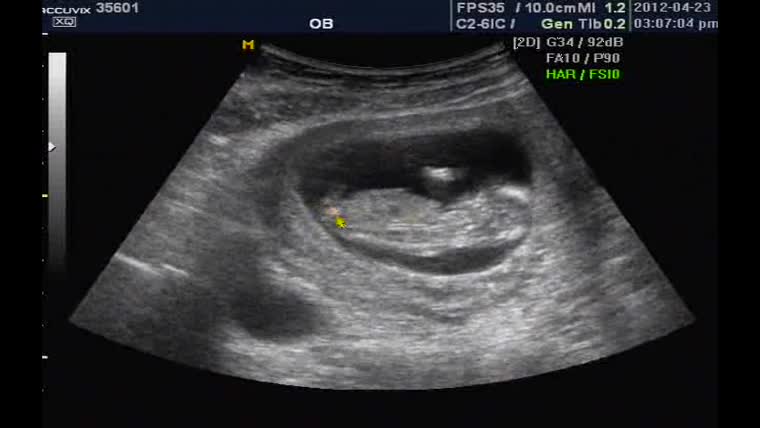

35601_baby.jpg (129.72 KB, 다운수: 635)

오현경 님이 2013-01-17 12:30에 등록 이름만 들어도 반가운 산모분! 그렇게 기다리던 덩이를 배에 품고 새벽에 오던날! 분만실에서 손 꼭 잡고, ...